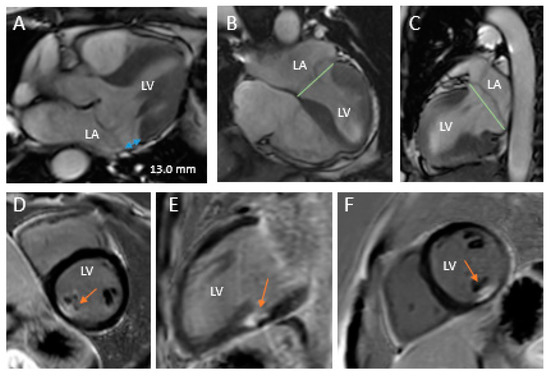

- Sturla, F.; Onorati, F.; Puppini, G.; Pappalardo, O.A.; Selmi, M.; Votta, E.; Faggian, G.; Redaelli, A. Dynamic and quantitative evaluation of degenerative mitral valve disease: A dedicated framework based on cardiac magnetic resonance imaging. J. Thorac. Dis. 2017, 9, S225–S238. [Google Scholar] [CrossRef]

- Essayagh, B.; Iacuzio, L.; Civaia, F.; Avierinos, J.F.; Tribouilloy, C.; Levy, F. Usefulness of 3-Tesla Cardiac Magnetic Resonance to Detect Mitral Annular Disjunction in Patients With Mitral Valve Prolapse. Am. J. Cardiol. 2019, 124, 1725–1730. [Google Scholar] [CrossRef]

- Han, Y.; Peters, D.C.; Salton, C.J.; Bzymek, D.; Nezafat, R.; Goddu, B.; Kissinger, K.V.; Zimetbaum, P.J.; Manning, W.J.; Yeon, S.B. Cardiovascular Magnetic Resonance Characterization of Mitral Valve Prolapse. JACC Cardiovasc. Imaging 2008, 1, 294–303. [Google Scholar] [CrossRef] [PubMed]

- Garg, P.; Swift, A.J.; Zhong, L.; Carlhäll, C.J.; Ebbers, T.; Westenberg, J.; Hope, M.D.; Bucciarelli-Ducci, C.; Bax, J.J.; Myerson, S.G. Assessment of mitral valve regurgitation by cardiovascular magnetic resonance imaging. Nat. Rev. Cardiol. 2020, 17, 298–312. [Google Scholar] [CrossRef] [PubMed]